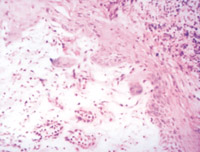

5-2-1 伤后第1天,,,,,,,表皮凝固性坏死,,,,,,,真皮浅层胶原纤维变性  HE×100